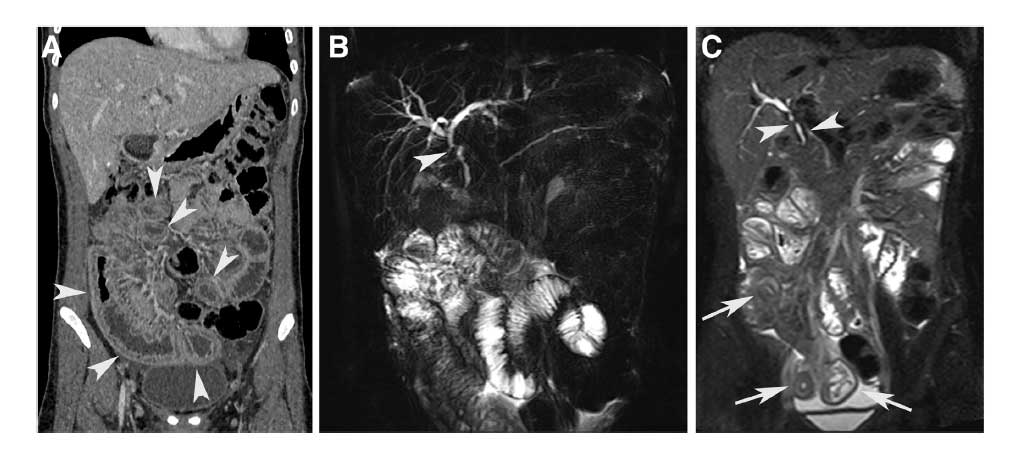

QUIZ: Espessamento do íleo e estenose biliar numa mulher brasileira de 26 anos